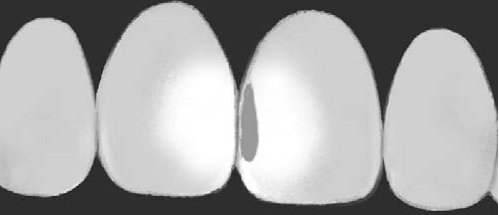

Caries inicial |

Hay una sombra gris,

que puede ser una línea fina < 2

mm de la misma anchura, hasta una franja

gris < 4 mm. |

Caries moderada |

Hay una amplia

sombra (> 5mm) gris / naranja / marrón / azulada / negra

cuando aplicamos luz. |

Sano |